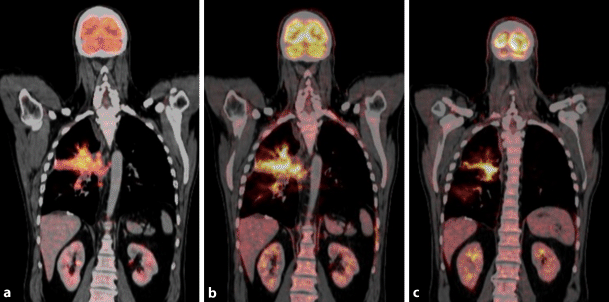

A special type of irAE is a sarcoid-like reaction that manifests with mediastinal und hilar lymphadenopathy and/or multiple micronodules or ground glass opacities [29]. Imaging features are characteristic; however, in clinical practice, the differentiation from PD, especially in pre-existing malignant mediastinal/hilar lymphadenopathy, might be challenging. In 18F-FDG-PET/CT imaging both micronodules and lymphadenopathy can show a considerably increase in FDG uptake (Fig. 3).

Fig. 3

Sarcoid-like reaction in a 77-year-old man with non-small cell lung cancer receiving immune checkpoint inhibitor therapy. ab Axial fluorodeoxyglucose positron emission tomography/computed tomography (18F-FDG-PET/CT) image obtained before therapy demonstrate a malignant right pleural effusion. c, d 4 weeks after treatment initiation, numerous intrapulmonary micronodules were detectable in both lungs, predominately right-sided. In addition, enlarged hilar/mediastinal lymph nodes with increased 18F-FDG newly developed, consistent with a sarcoid-like reaction. In contrast, malignant tumor burden resolved completely